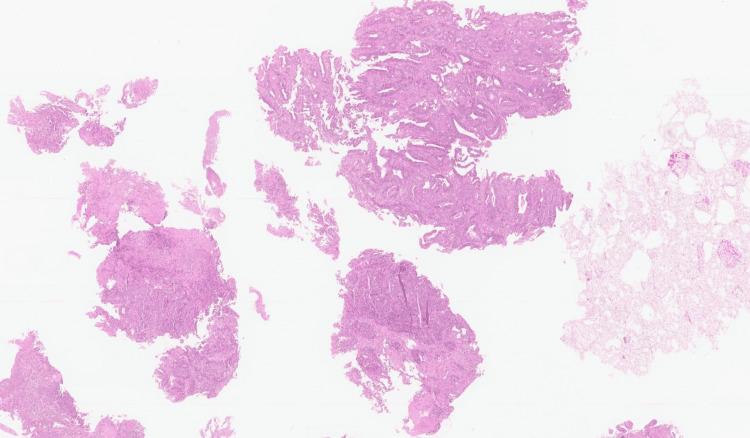

Celiac disease (CD) is an autoimmune disease triggered by gluten in the diet. The association between CD and increased risk of neoplasia is described mainly in patients diagnosed with CD and aged over 40 years or during the first years after CD diagnosis. Patients who remain symptomatic after 12 months of gluten-free diet should be screened to exclude neoplasms, especially lymphoma and gastrointestinal neoplasms. We report a case of small bowel adenocarcinoma (SBA) in a patient diagnosed with CD one year earlier.

乳糜泻(CD)是一种由饮食中的麸质引发的自身免疫性疾病。CD与肿瘤发生风险增加之间的关联主要见于年龄超过40岁的CD确诊患者或CD确诊后的最初几年。无麸质饮食12个月后仍有症状的患者应进行筛查以排除肿瘤,尤其是淋巴瘤和胃肠道肿瘤。我们报告一例小肠腺癌(SBA)病例,该患者一年前被诊断为CD。